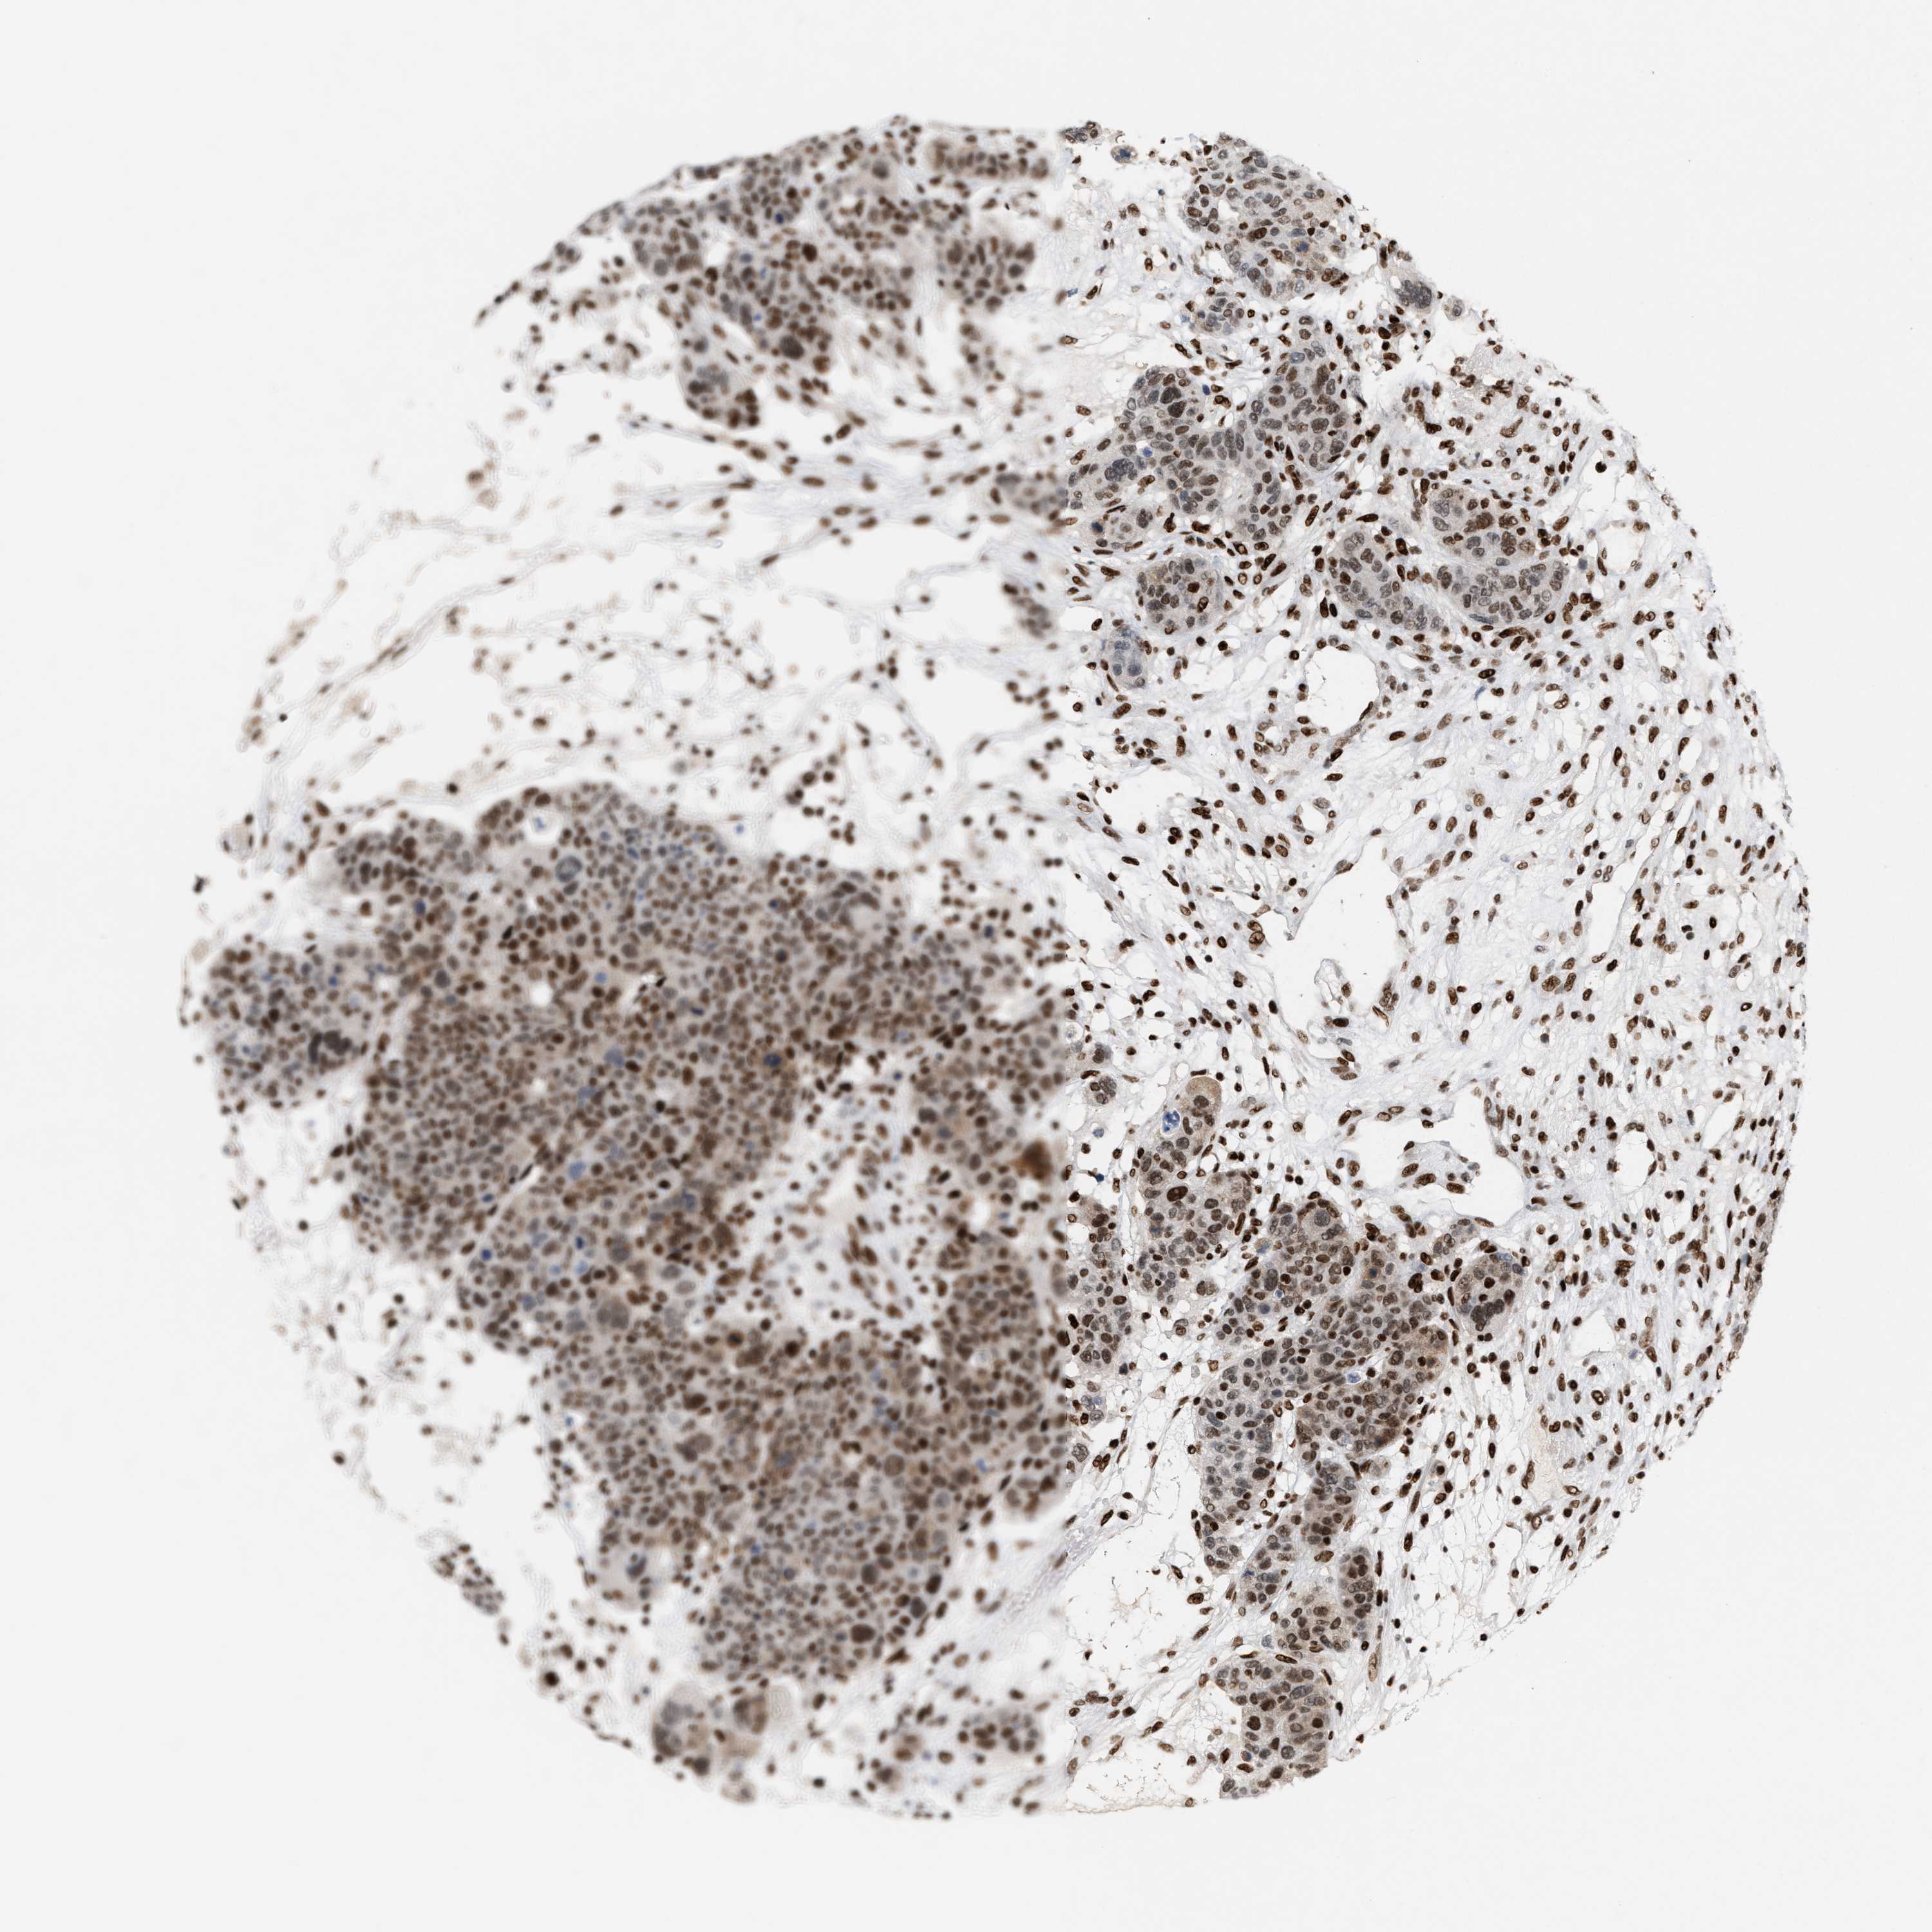

BRCA TCGA BRCA VALIDATION PROTEIN EXPRESSION